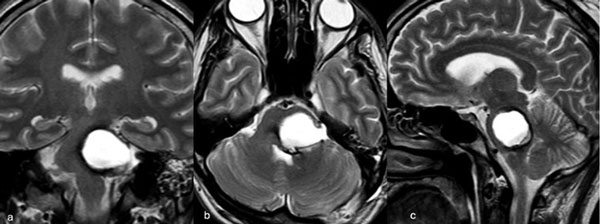

Figura 5. RM postquirúrgica de encéfalo. Se evidencia una exéresis completa con hiperintensidad en T2 en regresión. A, B y C) Imágenes ponderadas en T2 en cortes coronal, axial y sagital, respectivamente.

Caso 3: cavernoma pontino

Un hombre de 37 años, con antecedentes de hipertensión arterial, debutó con ataxia de la marcha, nistagmo y hemihipoestesia facial izquierda y braquiocrural derecha. La RM de encéfalo evidenció una malformación cavernomatosa centrada en la protuberancia y el pedúnculo cerebeloso medio izquierdo (Figura 6). Un mes después del sangrado, el paciente fue sometido a una exéresis de la lesión mediante un abordaje retrosigmoideo ampliado por izquierda a través del pedúnculo cerebeloso medio (Figura 7), logrando una exéresis completa (Figura 8). Después del procedimiento, el paciente evolucionó con persistencia de los síntomas de ingreso, pero sin agregar nuevos déficits.